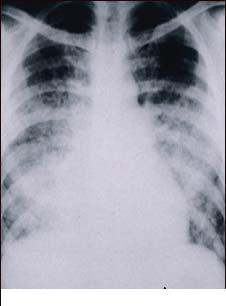

Varicela - varsat de vant (infectie contagioasa)